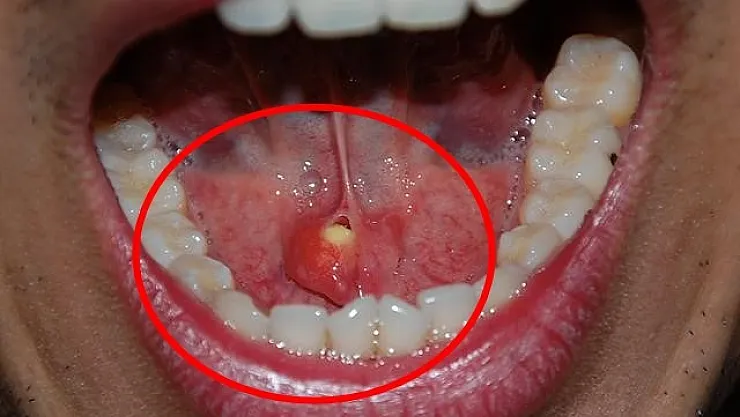

Tükürük bezi taşı hakkında bilgi veren Kulak, Burun ve Boğaz Hastalıkları Uzmanı Doç. Dr. Nesrettin Fatih Turgut, “Tükürük bezi taşları, çene altında ve yanak arkasında yerleşen tükürük salgısı üreten tükürük bezlerinde veya tükürük bezlerinin ağız içine açılmasını sağlayan tükürük bezi kanallarında görülen taşlardır. Büyük tükürük bezi olarak adlandırılan çene altı (submandibuler) ve yanak arkası (parotis) tükürük bezleri hastalıklarının yaklaşık olarak yarısını tükürük bezi taşları oluşturur. Tükürük içeriğinin yoğunluğu fazla olduğu için çene altı tükürük bezleri ve kanallarında 30-60 yaş aralığında, erkeklerde daha fazla görülmektedir. Yetersiz sıvı alımı, tükürük salgısının azalmasına neden olan enfeksiyonlar, ilaç kullanımı ve çeşitli enfeksiyonlar ve tükürük bezi kanallarının darlıkları tükürük bezi kanalı içinde taş oluşmasına yatkınlık oluşturur” dedi.

Taşların ağızdan dışarı atılmasındaki yöntemler hakkında da bilgilendirmede bulunan Doç. Dr. Nesrettin Fatih Turgut, “Bu hastalıkta tipik belirti, taşın var olduğu tarafta yer alan bezde yemek yeme sonrası gelişen şişlik ve ağrıdır. Tükürük salgısının dışarı atılamayıp birikimi, enfeksiyona yatkınlık oluşturur. Bakteriyel tükürük bezi iltihabı dediğimiz hastalık gelişebilir ki bu durumda şikayetler şiddetli hale gelebilir. Etkilenen tükürük bezinin aşırı şişmesi, aşırı hassasiyeti, ağrı ve ateş gelişebilir. Tedavi edilmediği takdirde, hastane yatışı gerektiren ve şiddeti daha fazla olan bir tabloya, derin boyun enfeksiyonuna, ilerleme görebiliriz. Şikâyetleri daha hafif olan ve taş boyutları küçük ve tükürük bezi kanalının ucuna yakın yerde yerleşim gösteren hastalarda geleneksel tedaviler önerilir. Ağrı kesiciler fayda sağlar. Bol sıvı tüketimi, ısı uygulaması rahatlama sağlayabilir. Bol sıvı tüketimini tüm hastalarımızda önermekteyiz. Aynı zamanda limon gibi ekşi ürünlerin emilmesi tükürük sıvısını artırır ve çok küçük taşların dışarı atılmasını sağlayabilir. Taş boyutunun büyük olması, taşında daha çok beze yakın yerde yerleşmiş olması durumlarında ise cerrahi uygulamaları gündeme gelmektedir. Taş yerleşimi, büyüklüğü etkilenen tükürük bezinin durumu cerrahinin şeklini belirler. Eğer taş tükürük bezi kanalında yer alıyorsa, sialendoskopi olarak adlandırılan kamera sistemi ile yer tespiti ve çıkarma işlemi herhangi bir kesi olmaksızın tercih edilir. Ancak taşın tükürük bezi içerisinde yer alması, boyutunun çok büyük olması durumlarında ise dışardan veya ağız içinden yaklaşım ile cerrahi seçenekleri gündeme gelmektedir” diye konuştu.